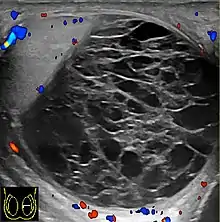

Varicocele

Varicocele refers to abnormal dilatation of the veins of the spermatic cord due to incompetence of valve in the spermatic vein. This results in impaired blood drainage into the spermatic vein when the patient assumes a standing position or during Valsalva's maneuver. Varicoceles are more common on the left side due to the following reasons (a) The left testicular vein is longer; (b) the left testicular vein enters the left renal vein at a right angle; (c) the left testicular artery in some men arches over the left renal vein, thereby compressing it; and (d) the descending colon distended with feces may compress the left testicular vein.

The US appearance of varicocele consists of multiple, hypoechoic, serpiginous, tubular like structures of varying sizes larger than 2 mm in diameter that is usually best visualized superior or lateral to the testis [Fig. 27a]. Color flow and duplex Doppler US optimized for low-flow velocities help confirm the venous flow pattern, with phasic variation and retrograde filling during a Valsalva's maneuver [Fig. 27b]. Intratesticular varicocele may appear as a vague hypoechoic area in the testis or mimics tubular ectasia. With color Doppler, this intratesticular hypoechoic area also showed reflux of vascular flow during Valsalva's maneuver [Fig. 28].